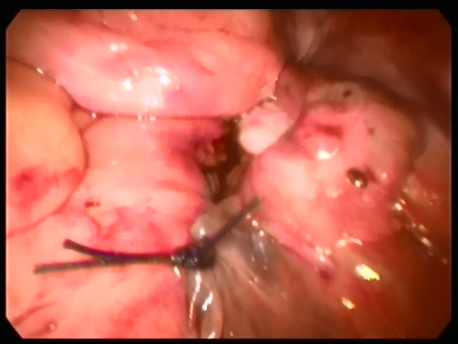

Although vaginal surgery and repair was preferred in older women, laparoscopic surgery has become the route of choice today. This is because vaginal repair utilizes already damaged tissue to repair the prolapse and, hence, the chance of failure of surgery and recurrence of prolapse over the long term is significantly higher.